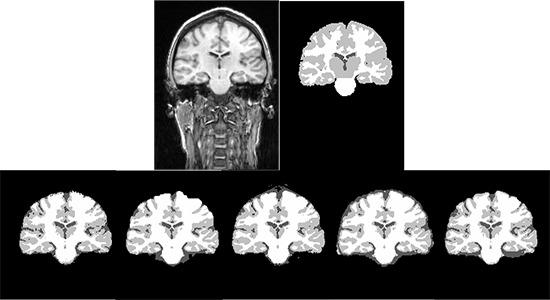

In this paper, performance evaluation of three widely used brain segmentation software packages SPM8, FSL and Brainsuite is presented. Segmentation with SPM8 has been performed in three frameworks: i) default segmentation, ii) SPM8 New-segmentation and iii) modified version using hidden Markov random field as implemented in SPM8-VBM toolbox.

The accuracy of the segmented GM, WM and CSF and the robustness of the tools against changes of image quality has been assessed using Brainweb simulated MR images and IBSR real MR images. The calculated similarity between the segmented tissues using different tools and corresponding ground truth shows variations in segmentation results.

本文对三种广泛使用的脑分割软件包SPM8、FSL和Brainsuite进行了性能评估。使用SPM8进行分割的框架有三种:i)默认分割,ii)SPM8新分割,iii)使用SPM8-VBM工具箱中实现的隐马尔可夫随机场的修改版本。

使用Brainweb模拟MR图像和IBSR真实MR图像评估了分割后的GM、WM和CSF的准确性以及工具对图像质量变化的鲁棒性。使用不同工具分割的组织与相应的真实情况之间计算出的相似度显示了分割结果的差异。